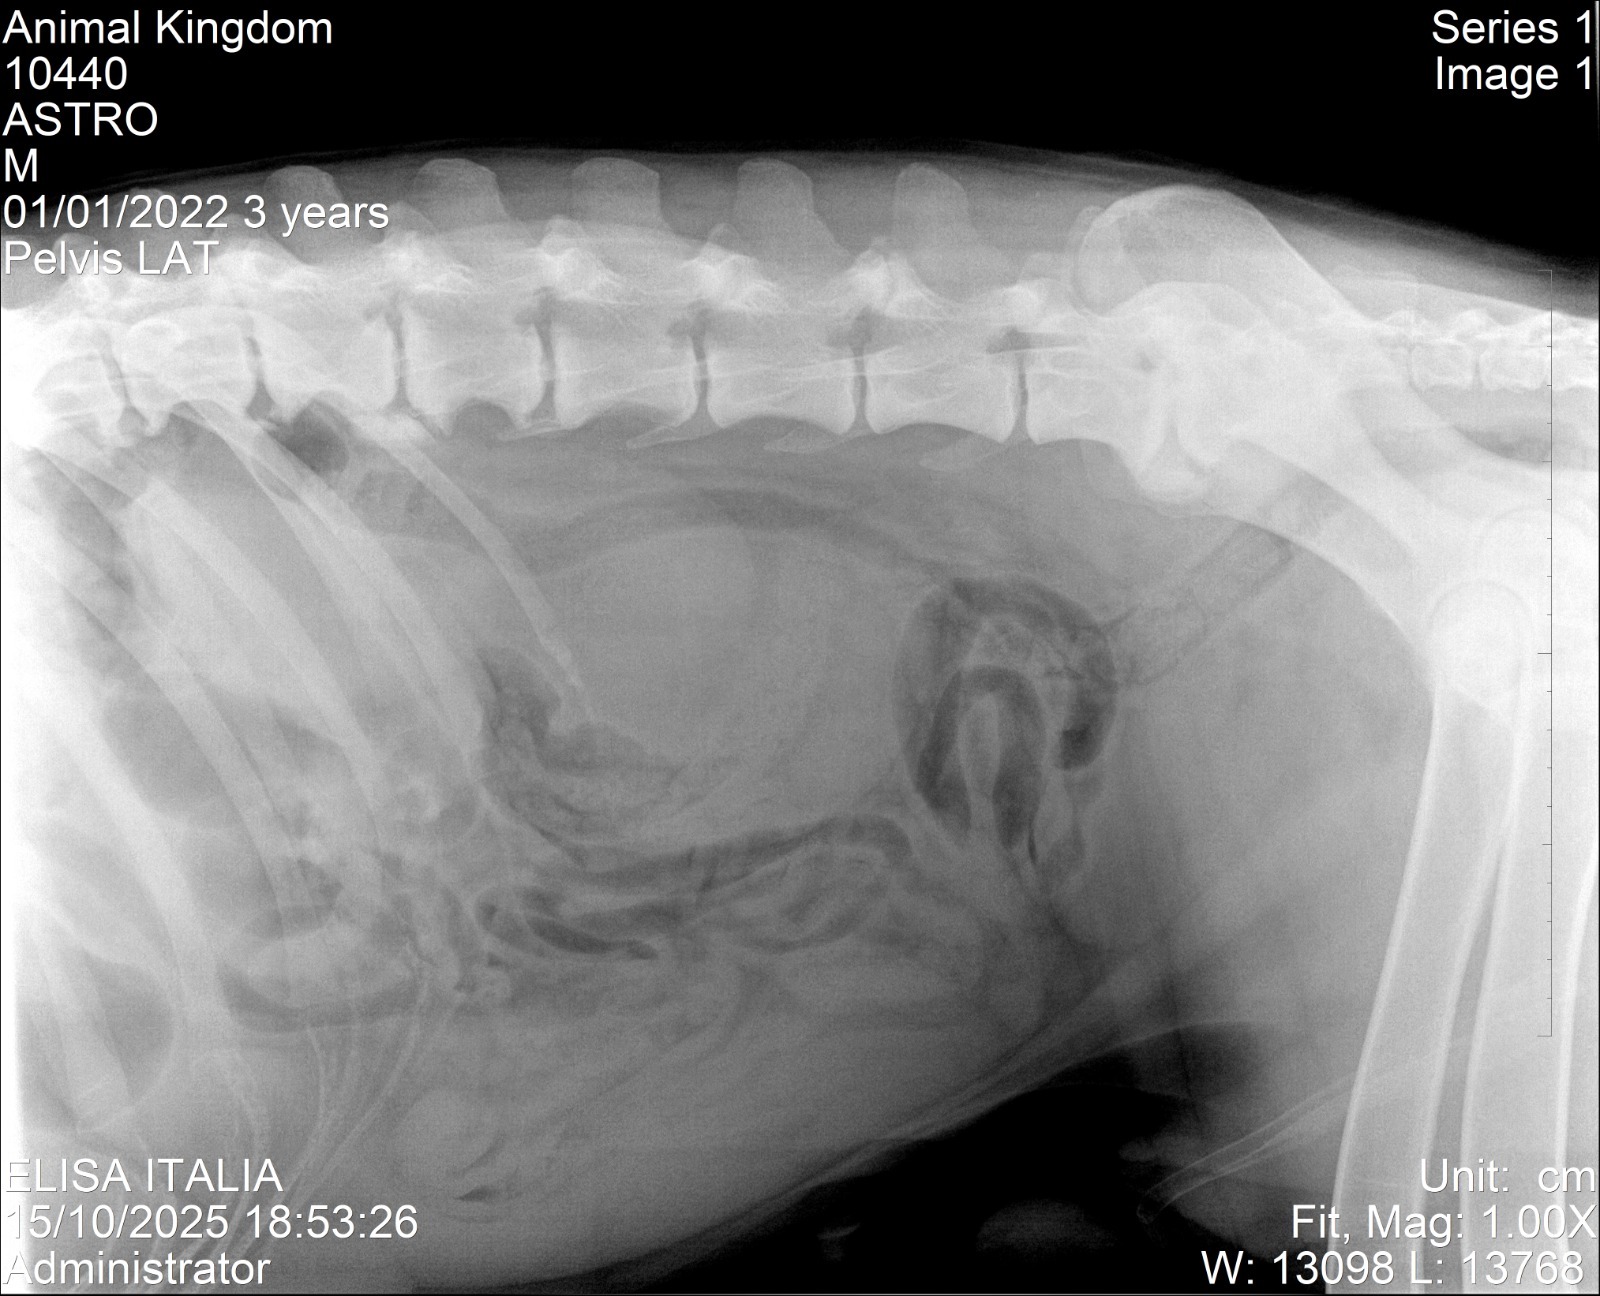

Astro es un perrito gigante y anciano que vive en nuestro refugio. Toda su vida ha ayudado en la rehabilitación de más perritos. Hace tres semanas sufrió la ruptura de un ligamento cruzado, y cuando se preparaba para su cirugía, los exámenes preoperatorios revelaron algo inesperado: una masa en su abdomen.

La operación tuvo que cancelarse, y tras nuevos estudios descubrimos que se trataba de un absceso interno. Astro tuvo que someterse primero a la cirugía de rodilla y luego a otra intervención para retirar la masa. Lamentablemente, durante su recuperación, el otro ligamento también se rompió, ya que todo su peso recaía sobre una sola pata.